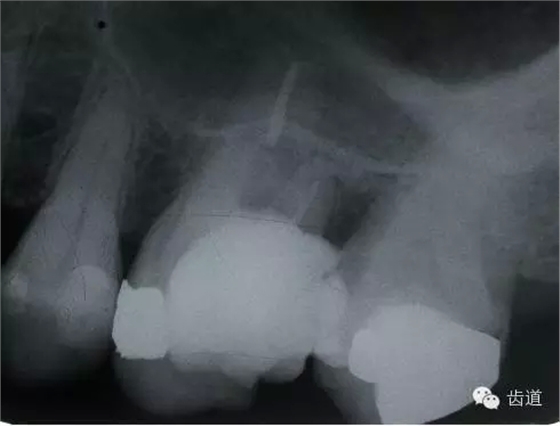

左下6底穿

左上6底穿